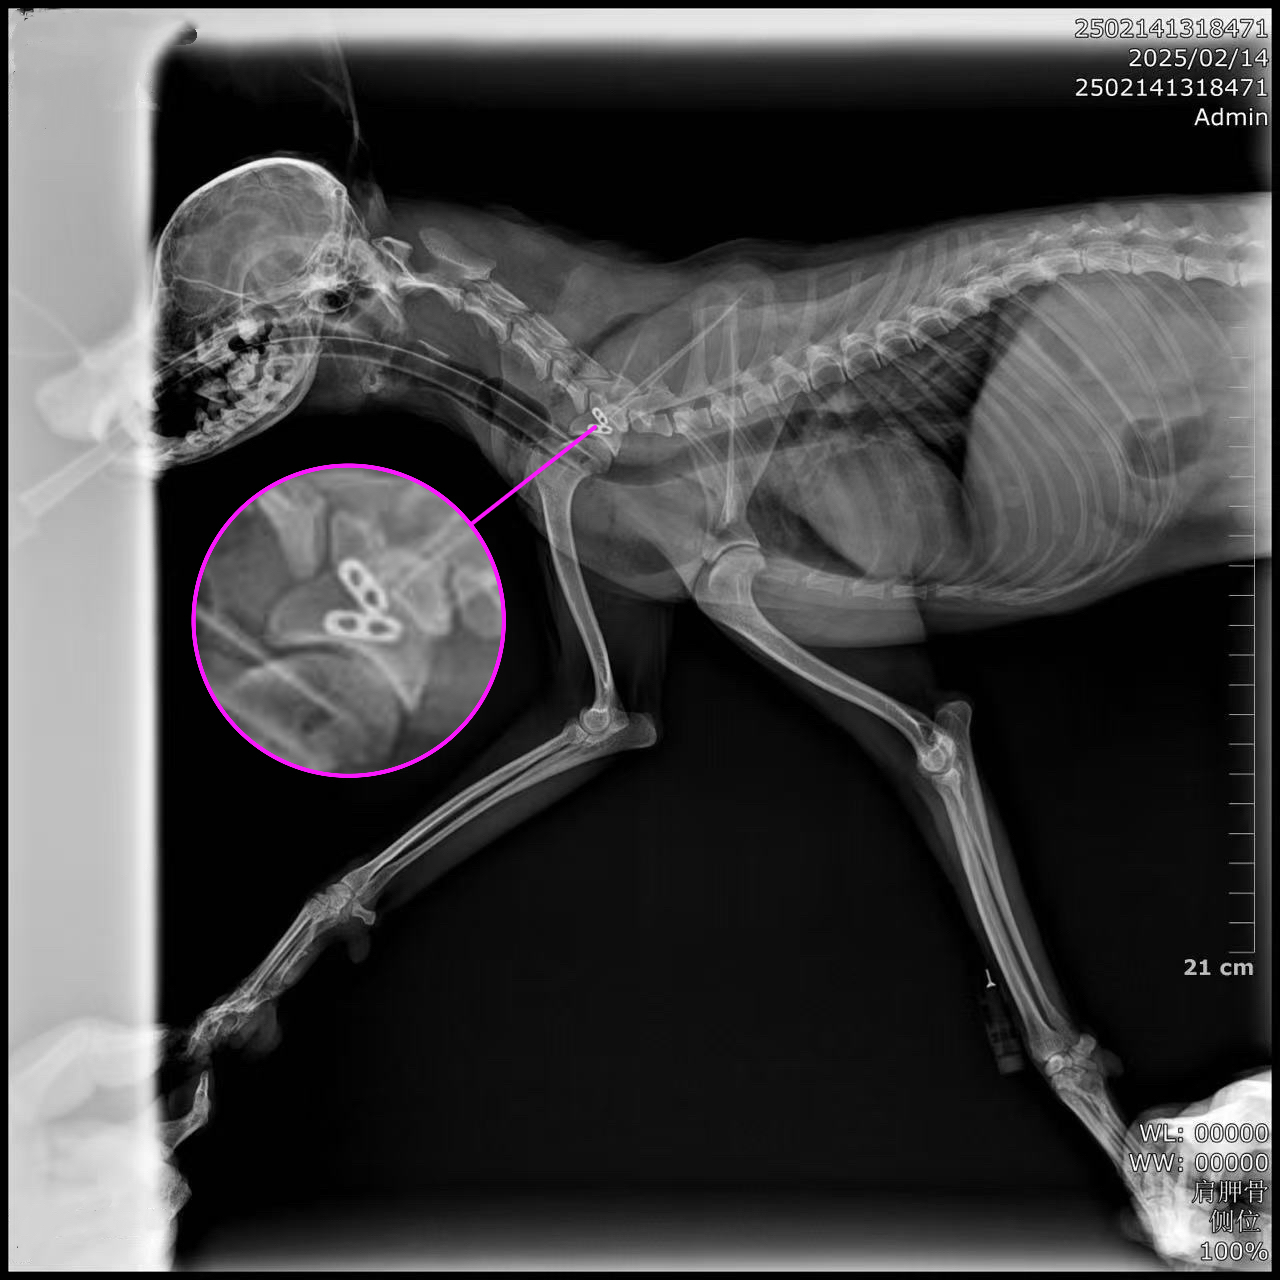

▼ Imaging

▼ Post-op Imaging